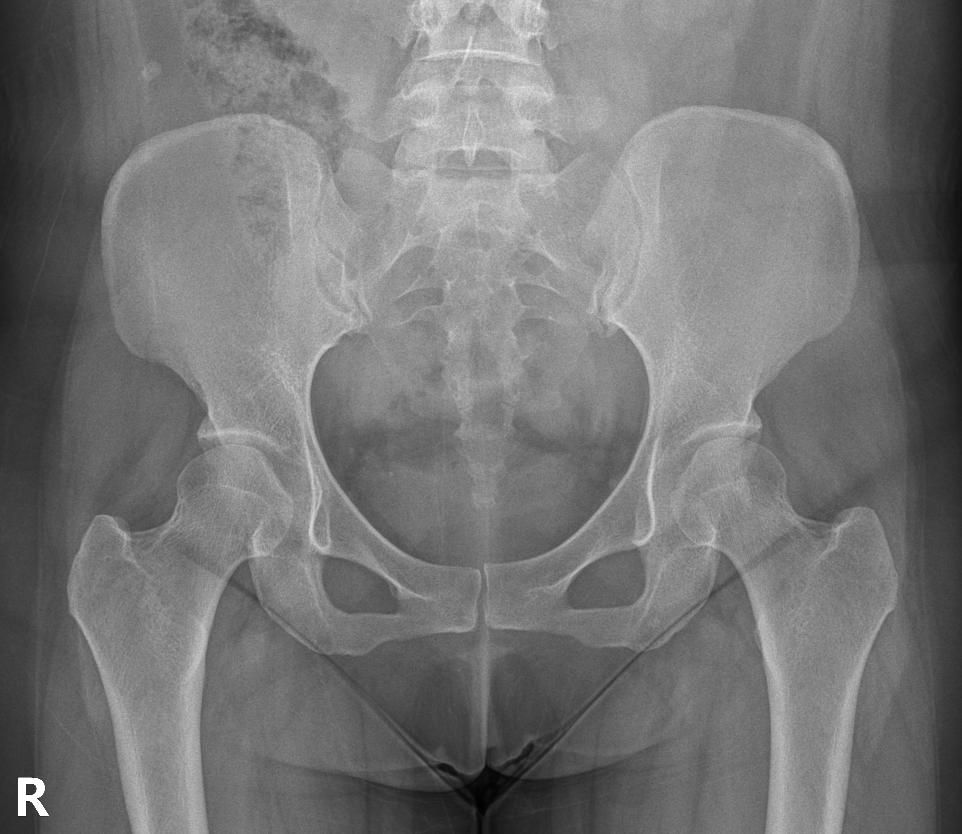

척추분리증인가요??(엑스레이 있어요)

한 병원에서는 척추분리증이라고 하고 한 병원에서는 척추분리증이 아니라고 해서요. 혹시 아래 사진에서 척추분리증 소견이 보이는 사진이 있나요??

여기까지가 a병원에서 찍은 사진이고 아래가 b병원에서 찍은 사진이에요!

• 7번 째 사진

• 8번 째 사진

• 9번 째 사진

척추분리증 맞습니다.

A병원 세번째 사진의 아래 부위에 척추분리증이 있는게 맞습니다.

B병원 사진에서는 비교적 흐리게 보이지만 잘 보면 B병원 엑스레이에서도 같은 부위에 분리증을 확인할 수 있습니다.

척추분리증은 척추의 특정 부위에서 척추뼈가 분리되거나 불안정해지는 상태를 의미합니다. 일반적으로 L5 척추뼈와 S1 엉덩뼈 사이에 발생하는 경우가 많고 이로 인해 허리 통증이나 신경 증상이 나타날 수 있어요! 따라서 두 병원에서의 진단이 다를 경우 추가적인 검사를 받거나 다른 전문의의 의견을 구하는 것이 좋습니다.